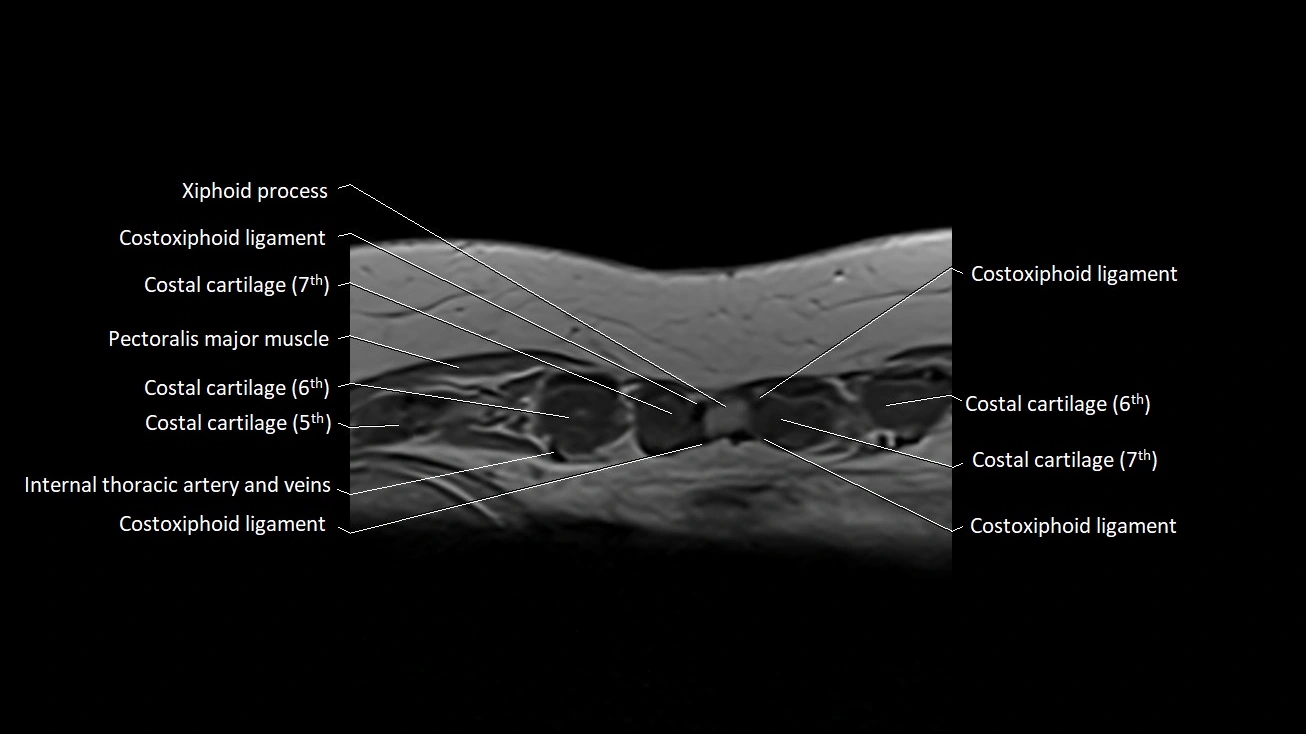

MRI images

image